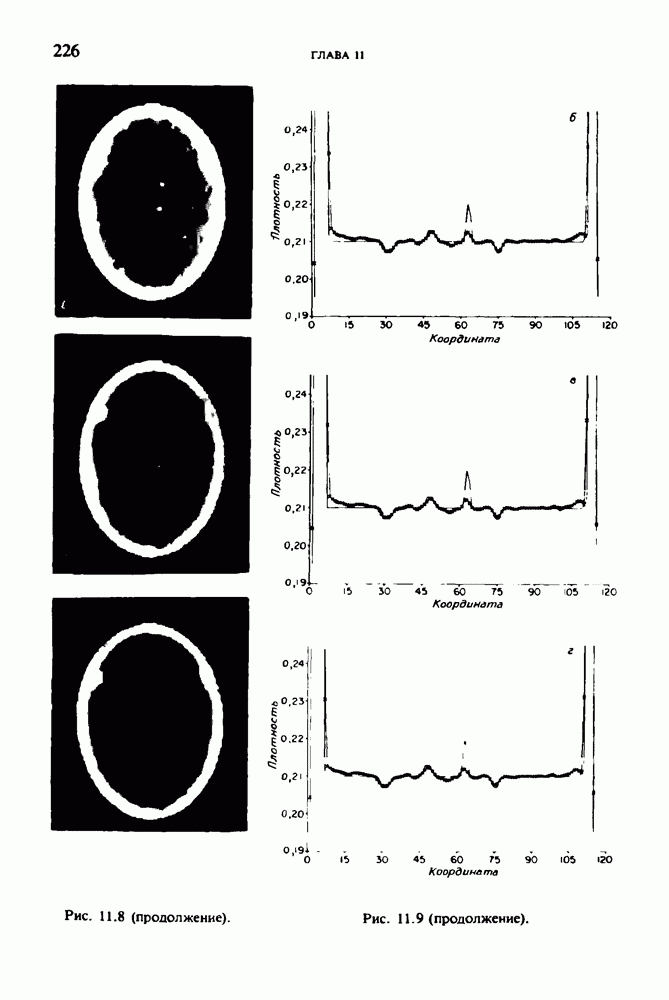

15.5. ЭКСПЕРИМЕНТАЛЬНЫЕ РЕЗУЛЬТАТЫ

Наш первый пример относится к случаю отображения системы желудочков головного мозга человека, которое было сделано по восьми смежным срезам толщиной На рис. 15.1 (вверху) приведены фрагменты из 80 х 80 элементов изображения трех из указанных срезов. Система желудочков изображена на фрагментах полностью. Размер элемента изображения в срезах составлял 1,5 х 1,5 мм, что соответствовало размеру элементарного

объема 1,5 х 1,5 х 8 мм, хотя более желательна, как и в предыдущих разделах, была бы кубическая форма элементарных объемов. Чтобы преобразовать элементарные объемы в кубические, использовалась линейная интерполяция данных для оценки 38 смежных срезов толщиной 1,5 мм. Таким образом, формируется массив из 80 х 80 х 32 чисел, характеризующих среднюю плотность множества элементарных объемов кубической формы.

Причина, по которой желудочки мозга выглядят более темными, чем окружающие ткани, состоит в том, что они содержат спинномозговую жидкость с несколько меньшим, чем у мозга, линейным коэффициентом ослабления (табл. 4.1). Поэтому диапазон значений, введенный в разд. 15.1, оказался таким, что его верхний предел стал больше, чем линейный коэффициент ослабления цереброспинальной жидкости, но меньшим, чем для самого мозга. Последнее означает, что все элементарные объемы, характеризующие спинномозговую жидкость, имеют числа Хаунсфилда в указанном диапазоне Таким образом, множество элементарных объемов, в которых числа Хаунсфилда лежат в диапазоне (разд. 15.2), содержит не только области желудочков, но также и другие части мозга, либо заполненные спинномозговой жидкостью, либо не заполненные ей, но имеющие по разным причинам такие же числа Хаунсфилда в данном диапазоне, например, вследствие наличия шума в исходных данных, артефактов при реконструкции и т.д. Элементарные объемы, которые принадлежат множеству изображены в виде светлых областей в нижней части рис. 15.1. Анатомическая картина соответствующих частей системы желудочков, показывающая в том числе положение corpora quadragemina («четверохолмие»), приведена на рис. 15.6.

Рис. 15.6. Анатомическая структура фрагмента системы желудочков головного мозга человека. 1 — передние рога латерального желудочка; 2 — третий желудочек; 3 — четверохолмие; 4 — задние рога латерального желудочка.

Рис. 15.7. (см. скан) Трехмерные проекции зарегистрированной поверхности системы желудочков головного мозга человека.

Для формирования трехмерного изображения системы желудочков (рис. 15.7) были использованы все рассмотренные в трех предыдущих разделах операции определения границ органов, исключения скрытых их частей поверхности и наложения теней. Число зарегистрированных граничных граней для системы желудочков составляло 8970, при этом регистрация множества из 80 х 80 х 38 элементарных объемов требует менее 0,5 мин машинного времени (на мини-ЭВМ типа Eclipse S/200).